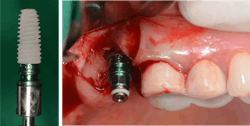

Hydraulic sinus lifting is a technological leap forward in sinus lift procedures. These innovative devices utilize hydraulic pressure to lift the sinus membrane gently and precisely, creating sufficient space for implant placement without the need for excessive bone manipulation (figure 3).

Hydraulic lifts can effectively prevent many of the aforementioned complications. Membrane perforations and injury to nearby vital structures are minimized because of the use of millimeter-precise drill stoppers, as well as simply using saline instead of blunt instruments to separate the thin sinus membrane. The flat-ended drills and stoppers in hydraulic techniques eliminate much of the guesswork involved in drilling to breach the sinus.

There is no manual bone manipulation, meaning hydraulics are less invasive and therefore promote faster healing for patients. Because mallets are not used, the patient experiences less trauma and doesn’t suffer related side effects such as tinnitus or concussions. Most importantly, unlike traditional methods that involve manual force, hydraulic lifts offer controlled and predictable elevation of the sinus floor, minimizing trauma to surrounding tissues and reducing postoperative complications.